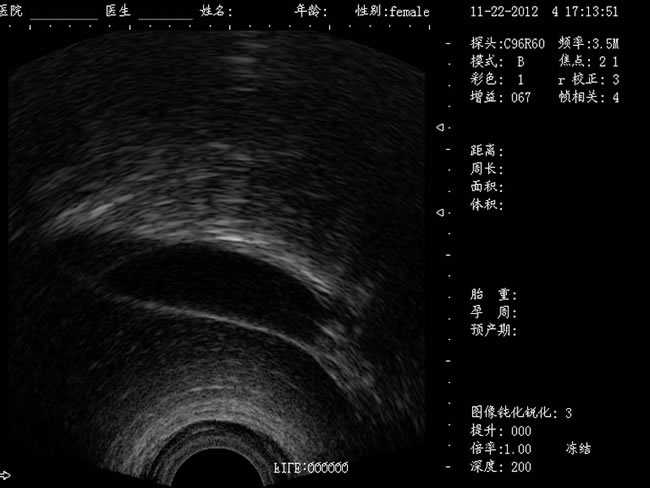

DW-460

功能特點:

婦產科手術監視儀-可視人流機掃描角度:

a) 6.5MHz腔內探頭:152º可視可調;

b) 3.5MHz凸陣探頭:60º可視可調;

TGC 調節:總增益、8 段TGC 調節器。

圖像放大:實時放大(16 級可調),局部放大(≥2 倍)。

圖像調節:黑白、左右、上下、亮度、對比度、焦點數、焦點間距、焦點位置、動態范圍、掃描角度、掃描線密度、聲功率、幀相關、M 速度。

圖像處理:圖像平滑/銳化、組織諧波、伽瑪校正、直方圖。

注釋功能:日期,時鐘,姓名,病歷號,性別,年齡,醫生、醫院、全屏幕字符編輯。

體位標記:≥30 種。